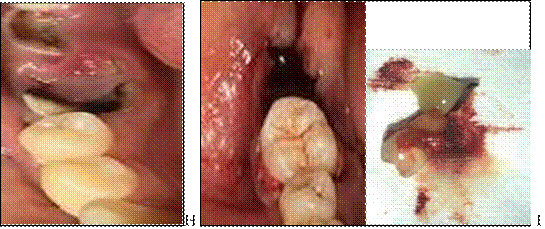

En la siguiente sección se da la evidencia fotográfica e imagenología de los procedimientos realizados en ambos casos y los resultados obtenidos en 13 y 8 semanas de evolución. (Ver anexos Figura 2 A y B)

Se observa en la imagen A, la destrucción coronaria; en la figura B, extracción propiamente dicha y alveoloplastia del futuro lecho receptor. (Ver Anexos Figura 3 C y D)

En la evaluación clínica, se pudo observar que la paciente presenta tejidos blandos normal, encía normal, color de contorno y consistencia normal. A dos meses de la cirugía, figura 6, se observó que no hay formación radicular y el tercer molar erupcionó. Se observa en la figura 8 H, la destrucción coronaria Caso 2; en la figura I, extracción propiamente dicha y alveoloplastia del futuro lecho receptor. (Ver Anexos Figura 9 J y K)

Figura 2. A y B: Fotografías reales del caso 1

Figura 3 C y D: Fotografías reales del caso 1

Figura 8 H y I: Fotografías reales del caso 2.